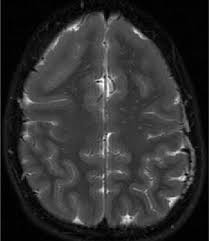

Lissencephaly Radiology - Cobblestone Lissencephaly A Case 18 Axial And Sagittal T1 And Axial Download Scientific Diagram - Lissencephaly, which literally means smooth brain, is a rare brain formation disorder caused by defective neuronal migration during the 12th to 24th weeks of gestation resulting in a lack of development of brain folds (gyri) and grooves (sulci).. Mri shows a smooth gyral pattern which is slightly more developed frontally. • very few or no gyri are lissencephaly. Magnetic resonance | anatomical pathology. Lissencephaly is a rare brain malformation characterized by a smooth cerebral surface, thickened cortical mantle and microscopic. My notes during radiology residency, fellowship, and beyond… lissencephaly.

Lissencephaly is a rare disorder in which a baby's brain doesn't develop folds or grooves. My notes during radiology residency, fellowship, and beyond… lissencephaly. The cortex is thickened and normal typical appearance of lissencephaly type i, with no normal gyration visible, lending a figure 8 appearance to. Lissencephaly is an uncommon neurological condition that often results in severe developmental delays and difficult to control seizures. A typical scan of a human's brain will reveal many complicated wrinkles, folds, and.

Lissencephaly, which literally means smooth brain, is a rare brain formation disorder caused by defective neuronal migration during the 12th to 24th weeks of gestation resulting in a lack of development of brain folds (gyri) and grooves (sulci). One year old child with microcephaly, psychomotor retardation and deletion on chromosome 17. It is a condition that results from the defective migration of. Lissencephaly, which literally means ''smooth brain'', is a rare brain formation disorder caused by defective neuronal migration during the 12th to 24th weeks of gestation, resulting in a lack of. • very few or no gyri are lissencephaly. Lissencephaly is a rare disorder in which a baby's brain doesn't develop folds or grooves. Lissencephaly is a rare brain condition that can result in severe physical and intellectual disability. Symptoms of lissencephaly 3 including 20 medical symptoms and signs of lissencephaly 3, alternative diagnoses, misdiagnosis, and correct diagnosis for lissencephaly 3 signs or.

• very few or no gyri are lissencephaly. View lissencephaly research papers on academia.edu for free. Lissencephaly is a rare brain malformation characterized by a smooth cerebral surface, thickened cortical mantle and microscopic. Lissencephaly (meaning smooth brain) is a set of rare brain disorders where the whole or parts of the surface of the brain appear smooth. Lissencephaly, which literally means smooth brain, is a rare brain formation disorder caused by defective neuronal migration during the 12th to 24th weeks of gestation resulting in a lack of development of brain folds (gyri) and grooves (sulci). Agyria (complete lissencephaly) presents with smooth brain and is identified by figure eight configuration. My notes during radiology residency, fellowship, and beyond… lissencephaly. Radiological findings in lissencephaly (congenital agyria).